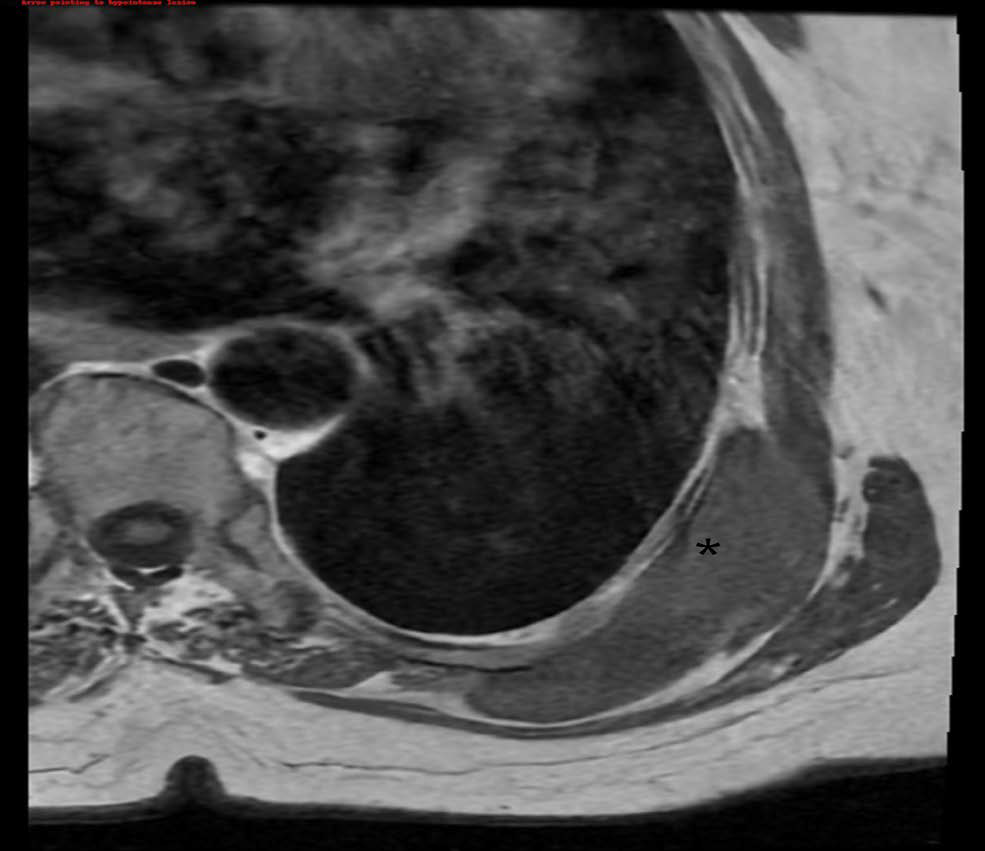

Utilizing Clinical Examination in Conjunction with Magnetic Resonance Cartilage Studies for Post-Operative Evaluation of Cartilage Repair: A Case Report

Stefanie Hui Ting Lee, Cynthia Assimta Peter, Steven Bak Siew Wong, Adriel Guang Wei Goh

1-10